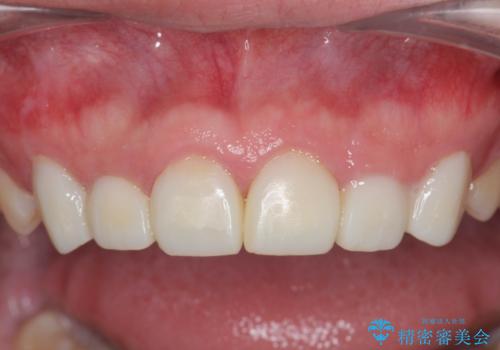

歯周外科を行い、歯ぐきの状態を整えた前歯セラミック治療

歯周外科を行ったことで、歯ぐきの形態や腫れが改善され、審美性だけでなく清掃性も大きく改善することができました。